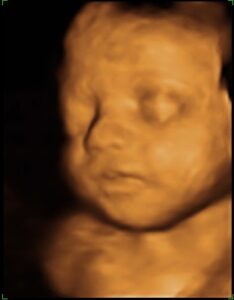

La ecografía 4D es mucho más que una imagen en movimiento: es una oportunidad única para conocer al bebé antes de su nacimiento y, al mismo tiempo, una herramienta médica avanzada que permite observar su desarrollo con gran precisión.

Gracias a la tecnología de alta resolución, podrás ver sus rasgos, sus movimientos e incluso sus gestos, viviendo una experiencia emocionante y cercana. Para el equipo médico, esta técnica ofrece una valiosa información sobre el bienestar fetal, la posición y el crecimiento del bebé, siempre con total seguridad para la madre y el futuro recién nacido.

Recomendamos realizar la ecografía 4D entre las semanas 26 y 32 de embarazo, el momento ideal para obtener las mejores imágenes.